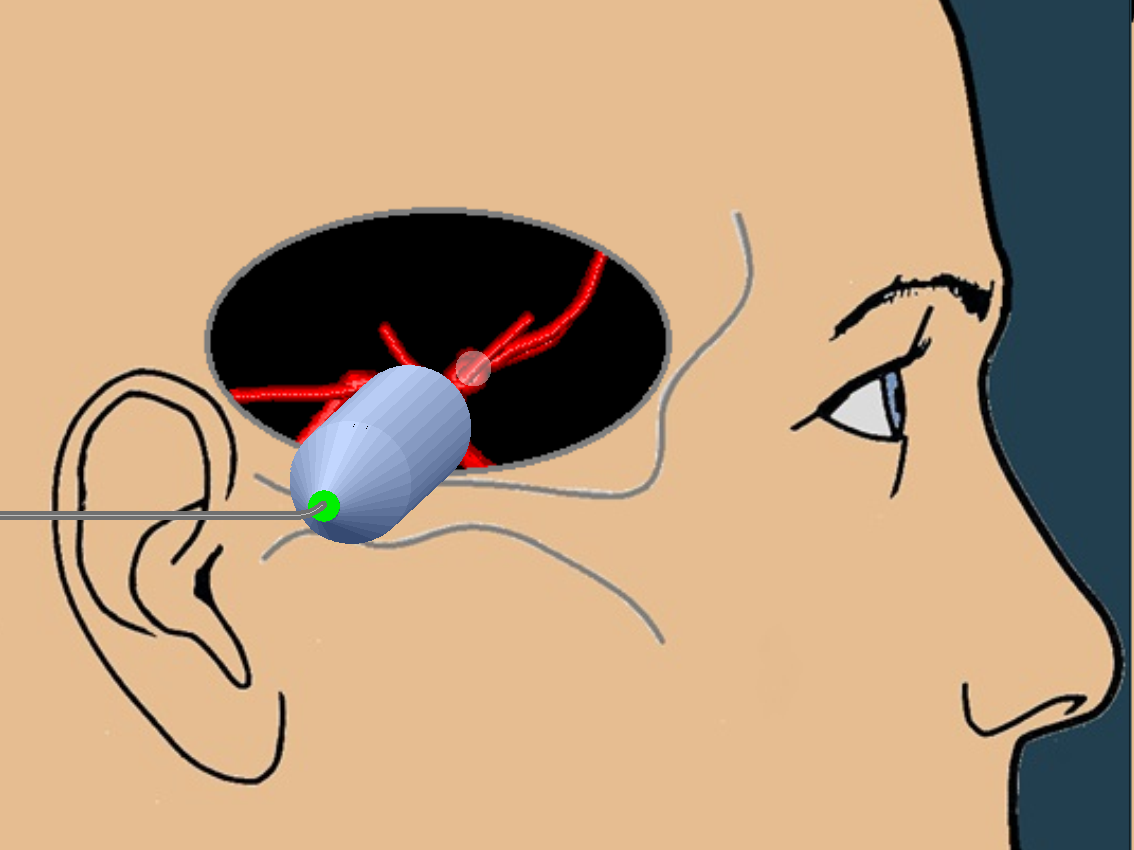

As always, I found the MCA with color doppler and put the pulse wave doppler gate on the proximal MCA.